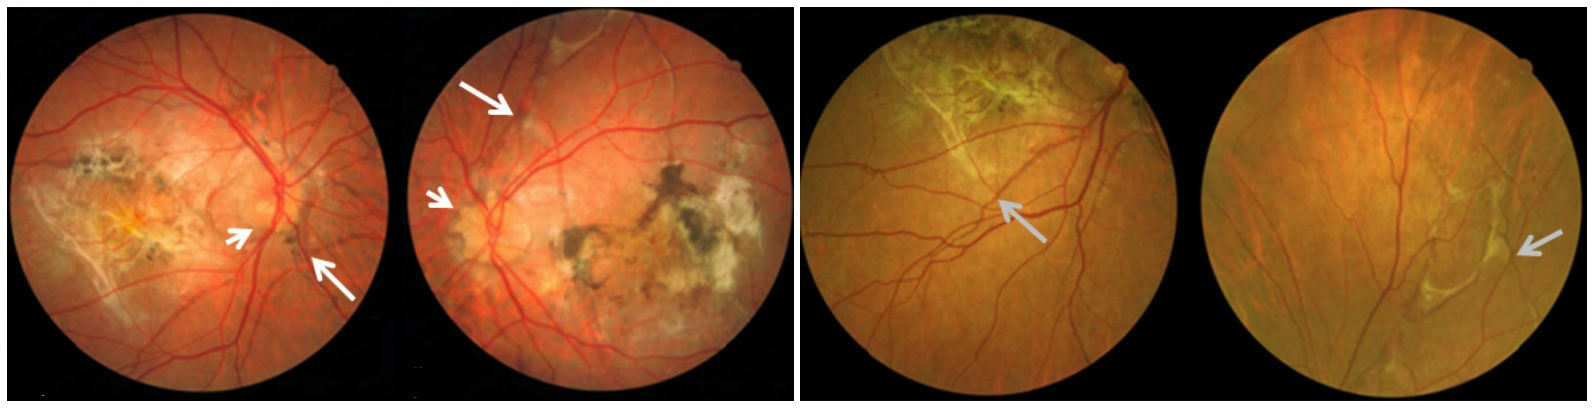

Медицинские исследования: эластическая псевдоксантома